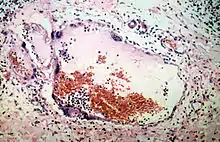

virus Nipah en las venas de los pulmones de un cerdo